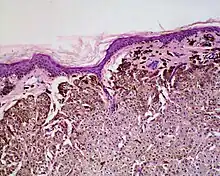

Histologically it is characterized by swollen, pale, polyhedral melanocytes, with pale cytoplasm and a central nucleus.[2] It is different to balloon cell melanoma,[3] which has larger nuclei and is structured like a melanoma.[1]

The characteristics of balloon cells include their relatively large sizes, small, round nuclei positioned in the center, and largely transparent cytoplasm.[3]

Examining under a microscope is particularly crucial when it comes to balloon cell nevi. Progressive vacuolization of melanocytes or nevus cells, caused by the enlargement as well as eventual destruction of melanosomes, results in the formation of balloon cells.[5]